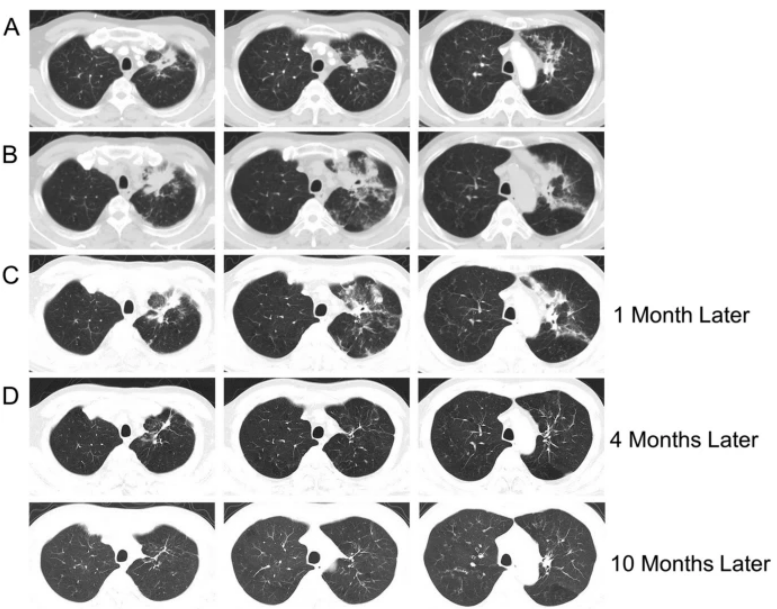

支气管镜在肺真菌病治疗中的应用主要有:①通畅气道:清除气道潴留物,解除机械阻塞。②冲洗引流:脓腔冲洗引流;液性病灶穿刺引流;炎症部位支气管冲洗;导管冲洗;穿刺引流。③局部用药:支气管冲洗、留置导管注药、药物缓释系统置入。病例:一名45岁男性因咳嗽、咳黄痰、呼吸困难持续5个月入院,患者胸部CT提示肿块引起的阻塞性肺不张(图3),但初步病理活检并未明确支持肿瘤诊断。这种不确定性可能与浅表取样有关,但不能完全排除肿瘤病变,使用硬质支气管镜检查缓解气道阻塞。术中见气道内白色肿块,该肿块松散地附着在支气管壁上(图4),镊子取出肿块时出血极少。肿块的组织学检查显示慢性化脓性炎症和肉芽肿形成、提示新型隐球菌感染。通过宏基因组二代测序证实了BALF中新生梭菌的存在。同时,血清隐球菌荚膜抗原检测结果呈阳性,氟康唑抗感染后痊愈。注:A:右主支气管和右中支气管有肿块,右下叶不张;B:右主支气管肿块消失,肺复张;C:右主支气管肿块完全消失和完全肺复张。图源:Medicine (Baltimore), 2024, 103(12):e37455.注:A:硬质支气管镜检查前软性支气管镜检查,显示右侧主支气管有肿块,导致闭塞;B:硬质支气管镜检查3天后软性支气管镜检查,证明成功从右侧主支气管中切除肿块。图源:Medicine (Baltimore), 2024, 103(12):e37455.隐球菌病胸部CT大部分表现为结节影,部分可有实变和坏死。支气管内隐球菌病导致的严重气道阻塞病例罕见,我们认为选择早期呼吸干预是一种理性的选择。首先,近一半的阻塞性支气管内隐球菌病患者对抗真菌药物反应不佳。其次,长期肺不张对肺复张构成挑战,可能导致永久性肺塌陷和肺功能受损,甚至最终导致肺实质感染和纤维化。软性支气管镜检查有助于区分内在性梗阻和外在压迫性,而硬质支气管镜检查可以更好地了解内在性梗阻性病变的性质,并提供一种气管内治疗手段。毛霉菌极易堵塞局部血管和支气管,病灶药物浓度低,单纯的全身药物治疗效果并不理想。近年来的研究发现两性霉素B局部给药,在抗真菌治疗方面会起到一定的辅助作用,包括雾化吸入、鞘内注射等,经支气管镜应用两性霉素B局部灌注对肺毛霉病可取得良好的效果。对于支气管被毛霉的菌丝体阻塞的患者,采用积极的介入治疗也可取得一定的效果,但应小心谨慎,防止出现大出血。各种介入治疗方法,包括两性霉素B局部灌注、冷冻治疗等,获得了不错的疗效。肺毛霉病的介入治疗必须具备全身麻醉、气管插管、预置球囊及有经验的呼吸内镜介入团队等。冷冻治疗建议在全麻气管插管方式下实施,出血风险高的患者还需要预置止血球囊。研究报道,10例肺毛霉病介入治疗患者均临床治愈,死亡0例。10例患者中应用冷冻探头冻取病灶8例,活检钳钳除病灶7例,套器套治疗2例,异物钳钳取病灶2例。介入和治疗经支气管镜直接局部灌注同步进行,1次/周,共1~6次。冷冻治疗的过程中3例患者预置球囊防止支气管内出血。10例患者中4级出血1例,3级出血2例,2级出血4例,3例患者无出血。支气管内出血均在5~10 min停止,术后少量痰中带血3~4天,术后气胸0例。牟向东教授团队在应用全身+局部治疗肺毛霉病的同时联合气管镜下介入技术清除阻塞气道和血管脓栓,并且在导航和超声定位下局部精准灌注两性霉素B,提高了肺组织内的药物浓度,降低了全身用药带来不良反应的概率,获得了显著的临床疗效,灌注后患者亦无明显不良反应(图5-图8)。注:右肺中叶和右肺下叶内基底段可见多发斑片影和片状肺内渗出实变影(箭头所示)。图源:https://www.btch.edu.cn/tszl/zbzx/fzjbzzzx/zb15blfx/91912.htm注:病理显示坏死组织内大量毛霉菌丝,并可见菌丝侵袭血管。